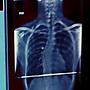

從X光判讀發現

胸椎有向右側彎 頸椎有次級向左側彎代償

推斷會有大小胸的問題:左胸>右胸

: http://i.imgur.com/zChcu50.jpg